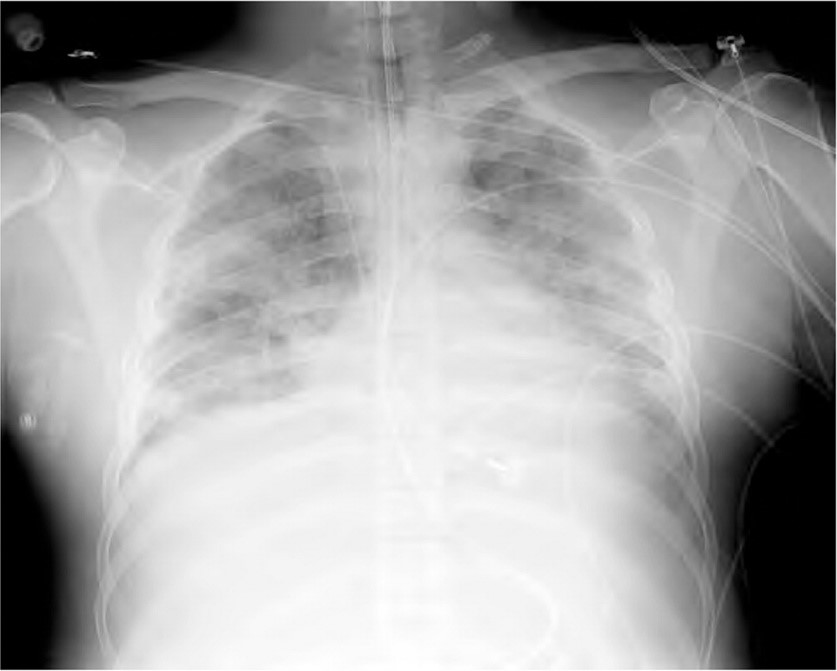

• New onset hypoxemia refractory to supplemental oxygen.

• Bilateral infiltrates on chest radiograph.

• Chest imaging: Presence of bilateral opacities in the chest imaging not completely explained by effusions, collapse, or the nodules.

Patients with ARDS represent a subset of a broader population of acute hypoxemic respiratory failure. The key difference between ARDS and acute hypoxemic respiratory failure is the requirement for bilateral infiltrates on chest imaging.